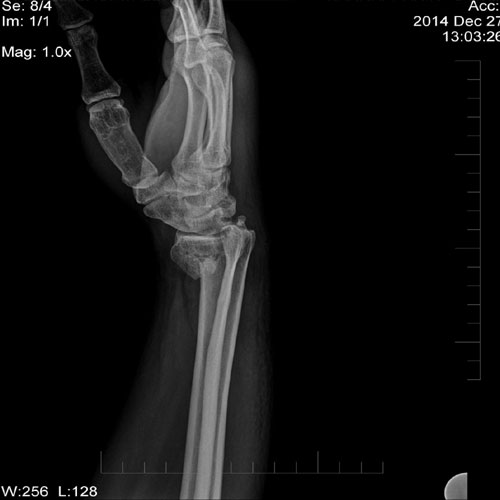

44 year old male with history of fall on outstretched hand. X ray of wrist joint showing Colle’s fracture.